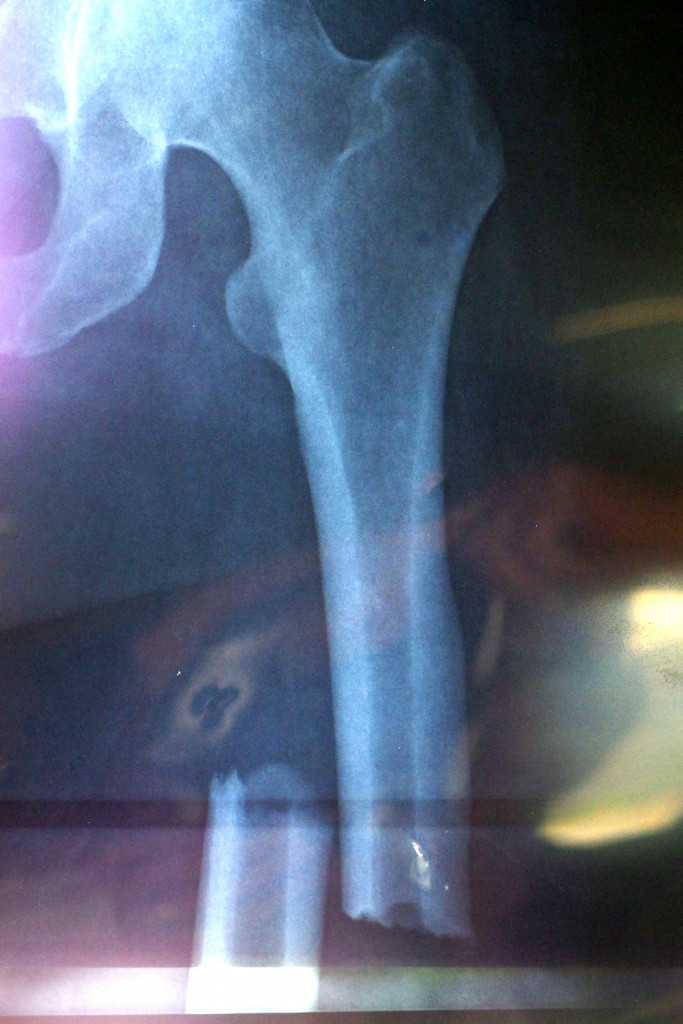

The Break x-ray (Ouch!)

It’s 11 weeks post my left femur break and surgery to insert a titanium rod from my hip to my knee.

In terms of diagnosis and investigation as to why my femur broke spontaneously (remember this is the longest, strongest bone in your body and it doesn’t just break as a rule), the Specialists are leaning towards a rare genetic bone disease called Osteopetrosis.

With Osteopetrosis there is a malignant infant version which is horrific and most babies don’t survive. Then there is an adult version which is milder and life expectancy is normal. With this disease the bone mass density is extremely high (mine is) and the bones then become brittle. As a result they either break or develop severe Osteoarthritis.